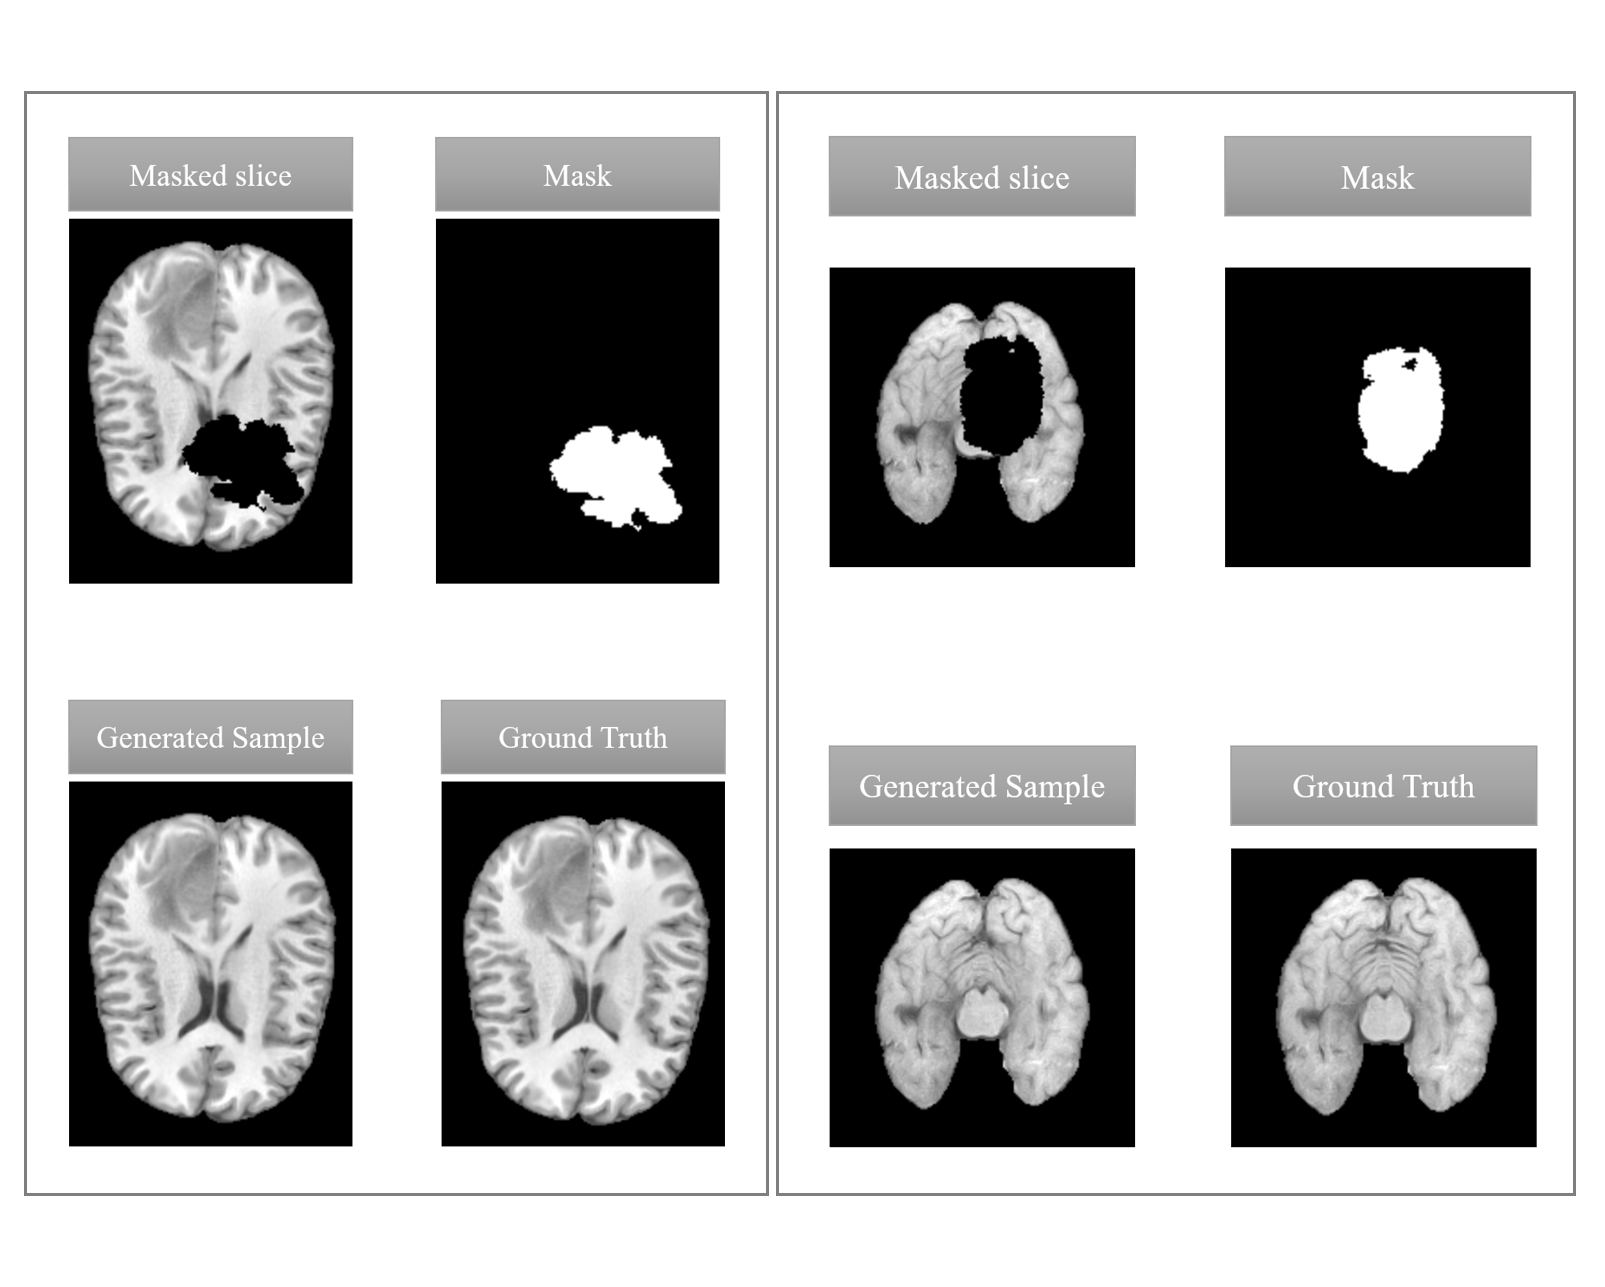

Figure 4: Exemplary 2D transversal slices. The 2D generated samples are of good quality. Moreover, they show a high similarity to the corresponding ground truth.

Figure 4 provides two examples of a given 2D masked image, the corresponding mask, the generated sample and the ground truth in the transversal view. In 2D, our approach manages to generate consistent results. However, if we look at the whole 3D volume, stripe artifacts can appear in the sagittal and coronal plane if multiple sequential slices are replaced within the volume. This is shown in the bottom left part of Figure 5. One possibility to reduce the visibility of these artifacts is the application of a Gaussian filter, shown in the bottom right part of Figure 5.